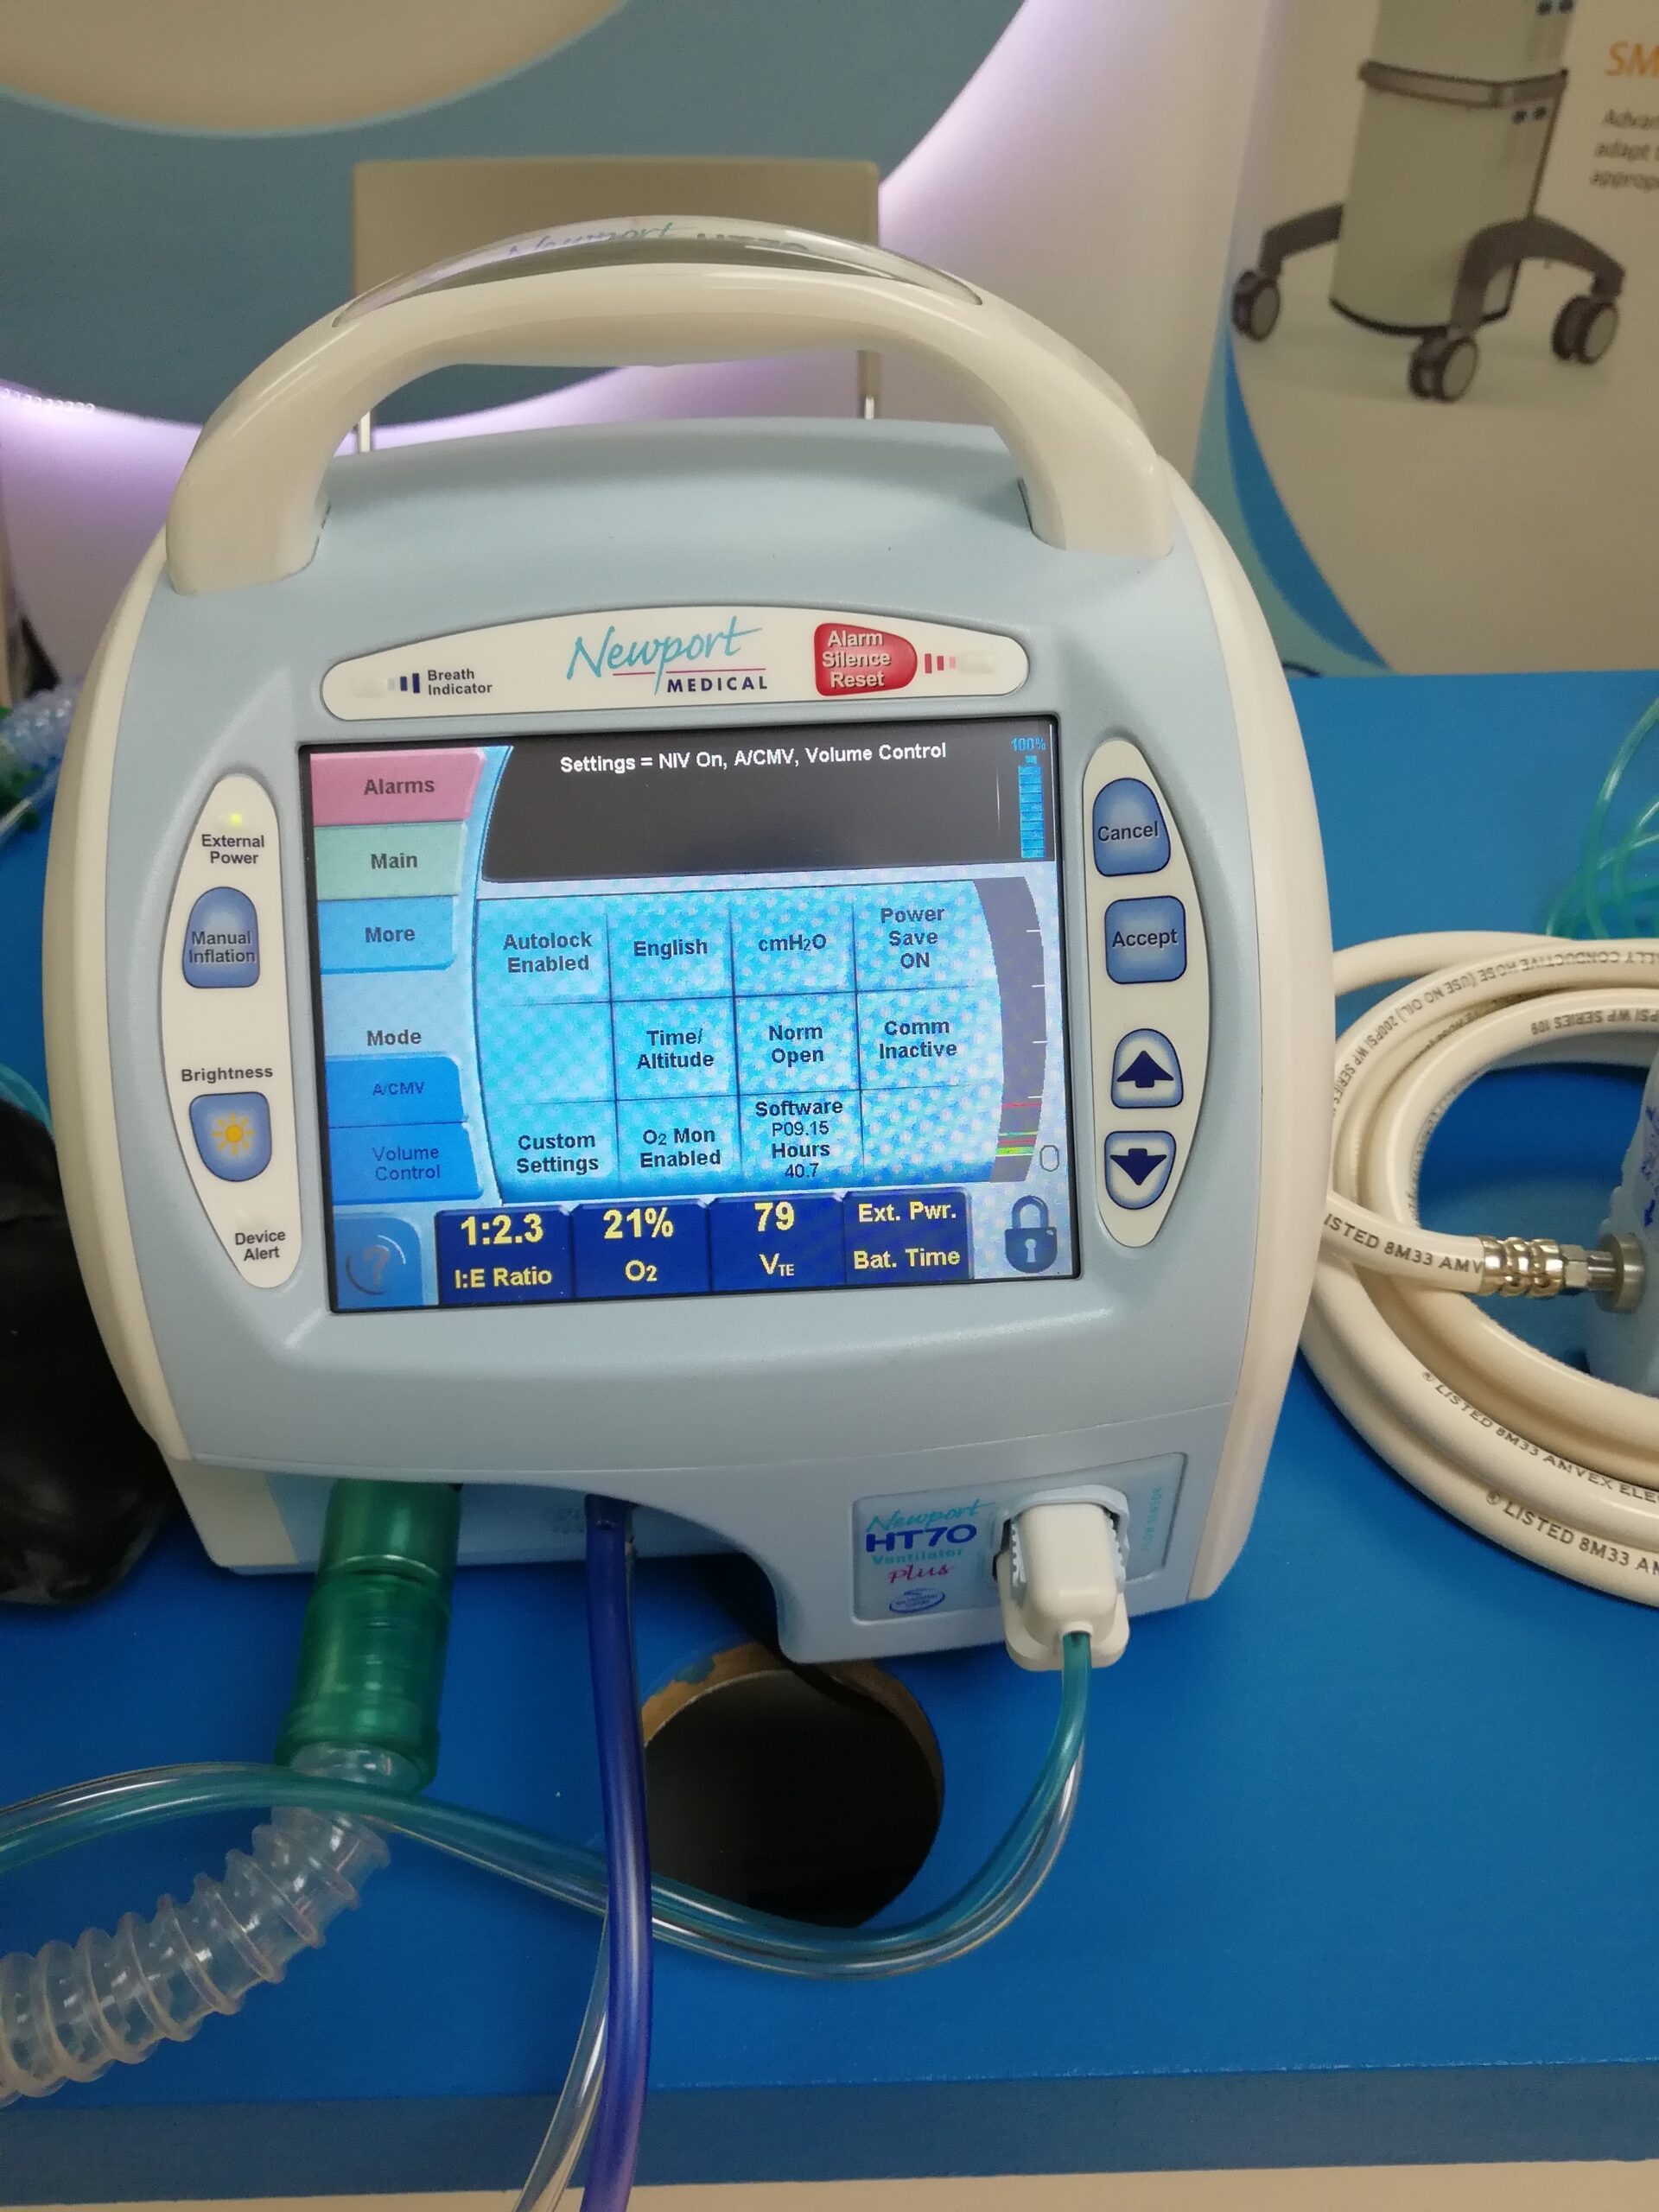

- Invasive Mechanical Ventilation – here a tracheostomy (insertion of a tube into the trachea from outside) is performed. It is only applied when the rest of the measures have failed (i.e., CPAP or NIV fails; deteriorating blood gases despite focused medical treatments) or conditions such as, clinical deterioration, sever respiratory acidosis or muscle fatigue. There are very high risks and complications of invasive mechanical ventilation and therefore it is only commenced in special cases and alway by a intensivist/specialist.

- Continuous positive airway pressure (CPAP) – machine supplied continuous positive pressure during the entire breathing cycle causing better oxygenation by narrowing the shunt (i.e., inadequate alveolar ventilation). This is generally using in high dependency units.

- Non-Invasive Ventilation – helps with the supply of bi-level positive airway pressure. This can be provided using simple or more sophisticated machines outside or inside high dependency units, respectively. It is one step down from invasive ventilation strategies.